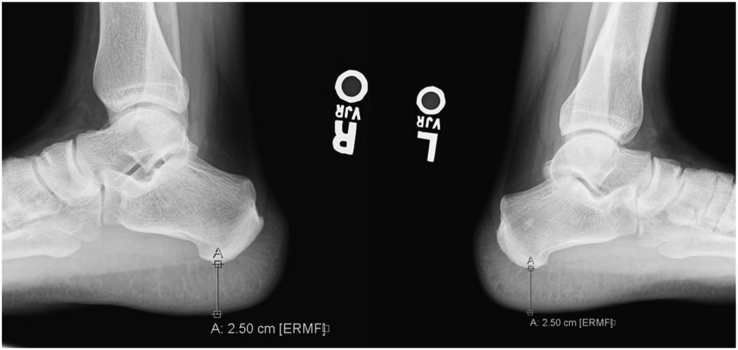

A 24-year-old man presented with blurry vision and bitemporal hemianopia for the past month. He also reported recent fatigue, depression, and decreased libido but denied any changes in glove or shoe size, hyperhidrosis, skin tags, galactorrhea, gynecomastia, muscle weakness, alopecia, heat/cold intolerance, abnormal weight changes, or palpitations. He reported no family history of pituitary adenoma, hyperparathyroidism, or pancreatic tumors. Physical examination was notable for mildly increased frontal bossing and jaw protrusion as noted in his driver’s license along with prominent thenar hypertrophy bilaterally. Pituitary magnetic resonance imaging showed a 2.6-cm partially cystic lesion arising from the pituitary fossa (Fig. 1). Laboratory studies showed the following: (1) insulin-like growth factor 1 (IGF-1) level of 633 ng/mL (reference, 109-353), (2) growth hormone (GH) level of 6.2 ng/mL (reference, 0.0-10.0), (3) prolactin level of 30.6 ng/mL (reference, 4.04-15.2), (4) serum cortisol level of 16.7 mcg/dL (reference, >10), (5) corticotropin level of 41 pg/mL (reference, 7.2-63.3), (6) total testosterone level of 284 ng/dL (reference 264-916), free thyroxine level of 1.03 ng/dL (reference 0.93-1.7), and (7) thyroid-stimulating hormone level of 1.58 mcIU/mL (reference 0.27-4.2). Hand radiographs showed hypertrophied terminal phalangeal tufts (Fig. 2). Lateral ankle radiographs showed a heel pad thickness of 25 mm (reference, <23) (Fig. 3).

Fig 3.